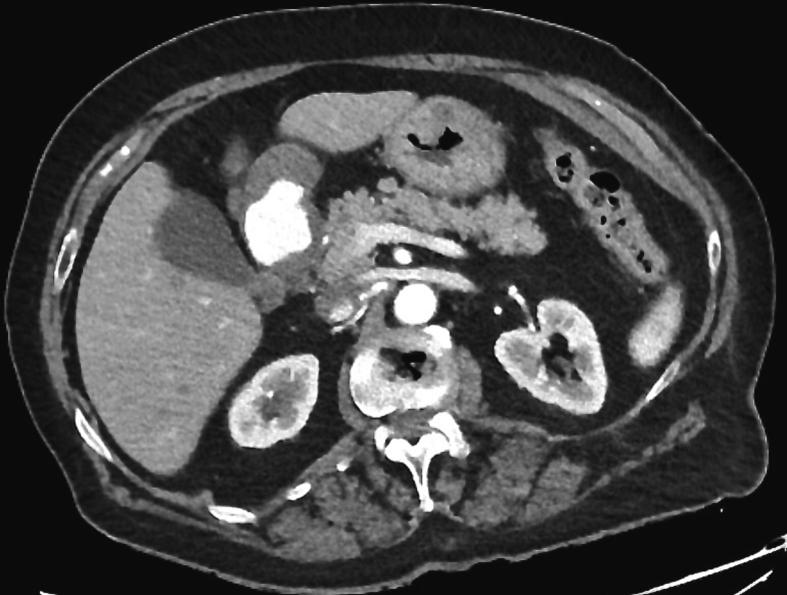

PRESENTATION OF CASE

We report the case of an 82-years-old female presenting with abdominal pain and hematemesis. Upper gastrointestinal endoscopy retrieved a large duodenal mass and subsequent CT scans identified a large GAA with contrast extravasation. Endovascular procedure included selective arteriography, microcatheterization, and embolization.

我们报告了一例82岁女性,表现为腹痛和呕血。上消化道内镜检查发现十二指肠有一个大肿块,随后的CT扫描确定为一个大的GAA并伴有造影剂外渗。血管内治疗包括选择性动脉造影、微导管插入和栓塞。